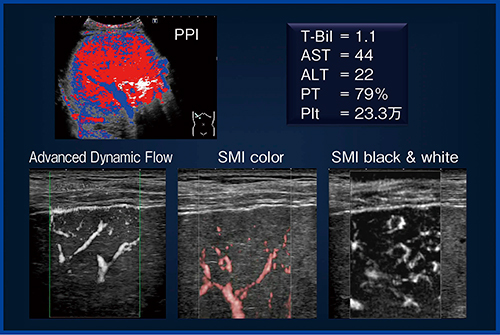

●症例3:48歳,男性,

アルコール性肝硬変(図6)

SMIでは,シャント様不整血管が多く認められる。ソナゾイド造影超音波(perfusion parametric imaging:PPI)では赤く描出される範囲が広く,門脈と動脈のバランスが動脈に傾いていることがわかる。

図6 症例3:48歳,男性,アルコール性肝硬変